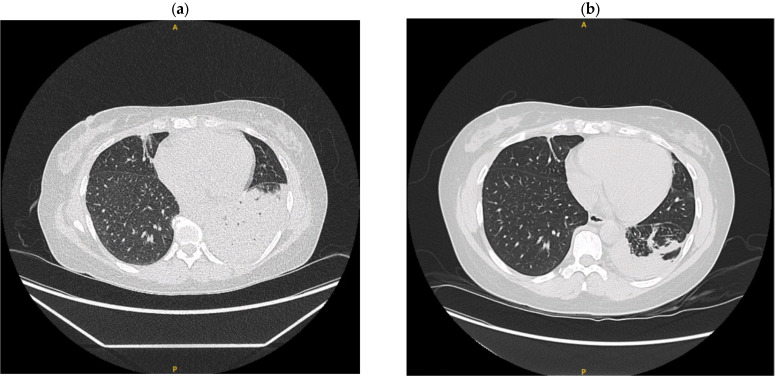

Anticytokine autoantibodies (AAbs), particularly anti-interferon-gamma (anti-IFN-γ) AAbs, disrupt cytokine functions, leading to infections, autoimmune-like diseases, and conditions resembling interleukin-12 (IL-12)/IFN-γ pathway defects. Advances in genetic testing have clarified overlaps between autoinflammatory, autoimmune disorders, and primary immunodeficiencies but reveal complex phenotypes and pathways. While these insights deepen our understanding of immune mechanisms, they also complicate diagnosis and treatment, with limited options for IFN-γ deficiencies caused by genetic mutations. The adult-onset immunodeficiency with disseminated lymphadenitis due to nontuberculous mycobacteria (NTM) and other opportunistic infections has been linked to high levels of anti-IFN-γ AAbs. This syndrome, initially identified in HIV-negative Asian patients, frequently affects individuals of Asian descent and may be associated with specific human leukocyte antigen (HLA) alleles. The presence of neutralizing anti-IFN-γ AAbs impairs the IFN-γ-dependent immune response, likely contributing to the persistent NTM infection. This study underscores the potential for late-onset anti-IFN-γ AAb syndrome to manifest with disseminated NTM (dNTM) infections, highlights the importance of timely diagnosis and considers rituximab as a potential therapeutic option.